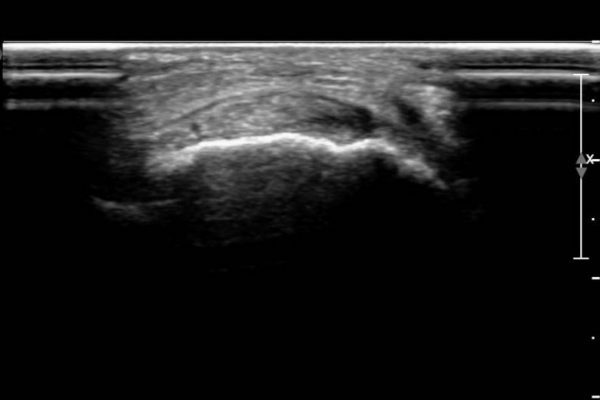

ÃÊÀ½ÆÄ ¼Ò°ß :  Àü°æ°ñ°Ç Á¾´Ü¸é°Ë»ç¿¡¼­ Àü°æ°ñ°ÇÀÌ °í¿¡ÄÚ¼¶À¯È­(hyperechoic fibrillar pattern) ¾ç»óÀ¸·Î °üÂûµÇ´Âµ¥

¼³Çü°ñ ºÎÂûºÎ¿¡¼­ °æ¹ÌÇÑ Á¦¿¡ÄÚ ¾ç»óÀÌ °üÂûµÈ´Ù(»çÁø 1, 2).